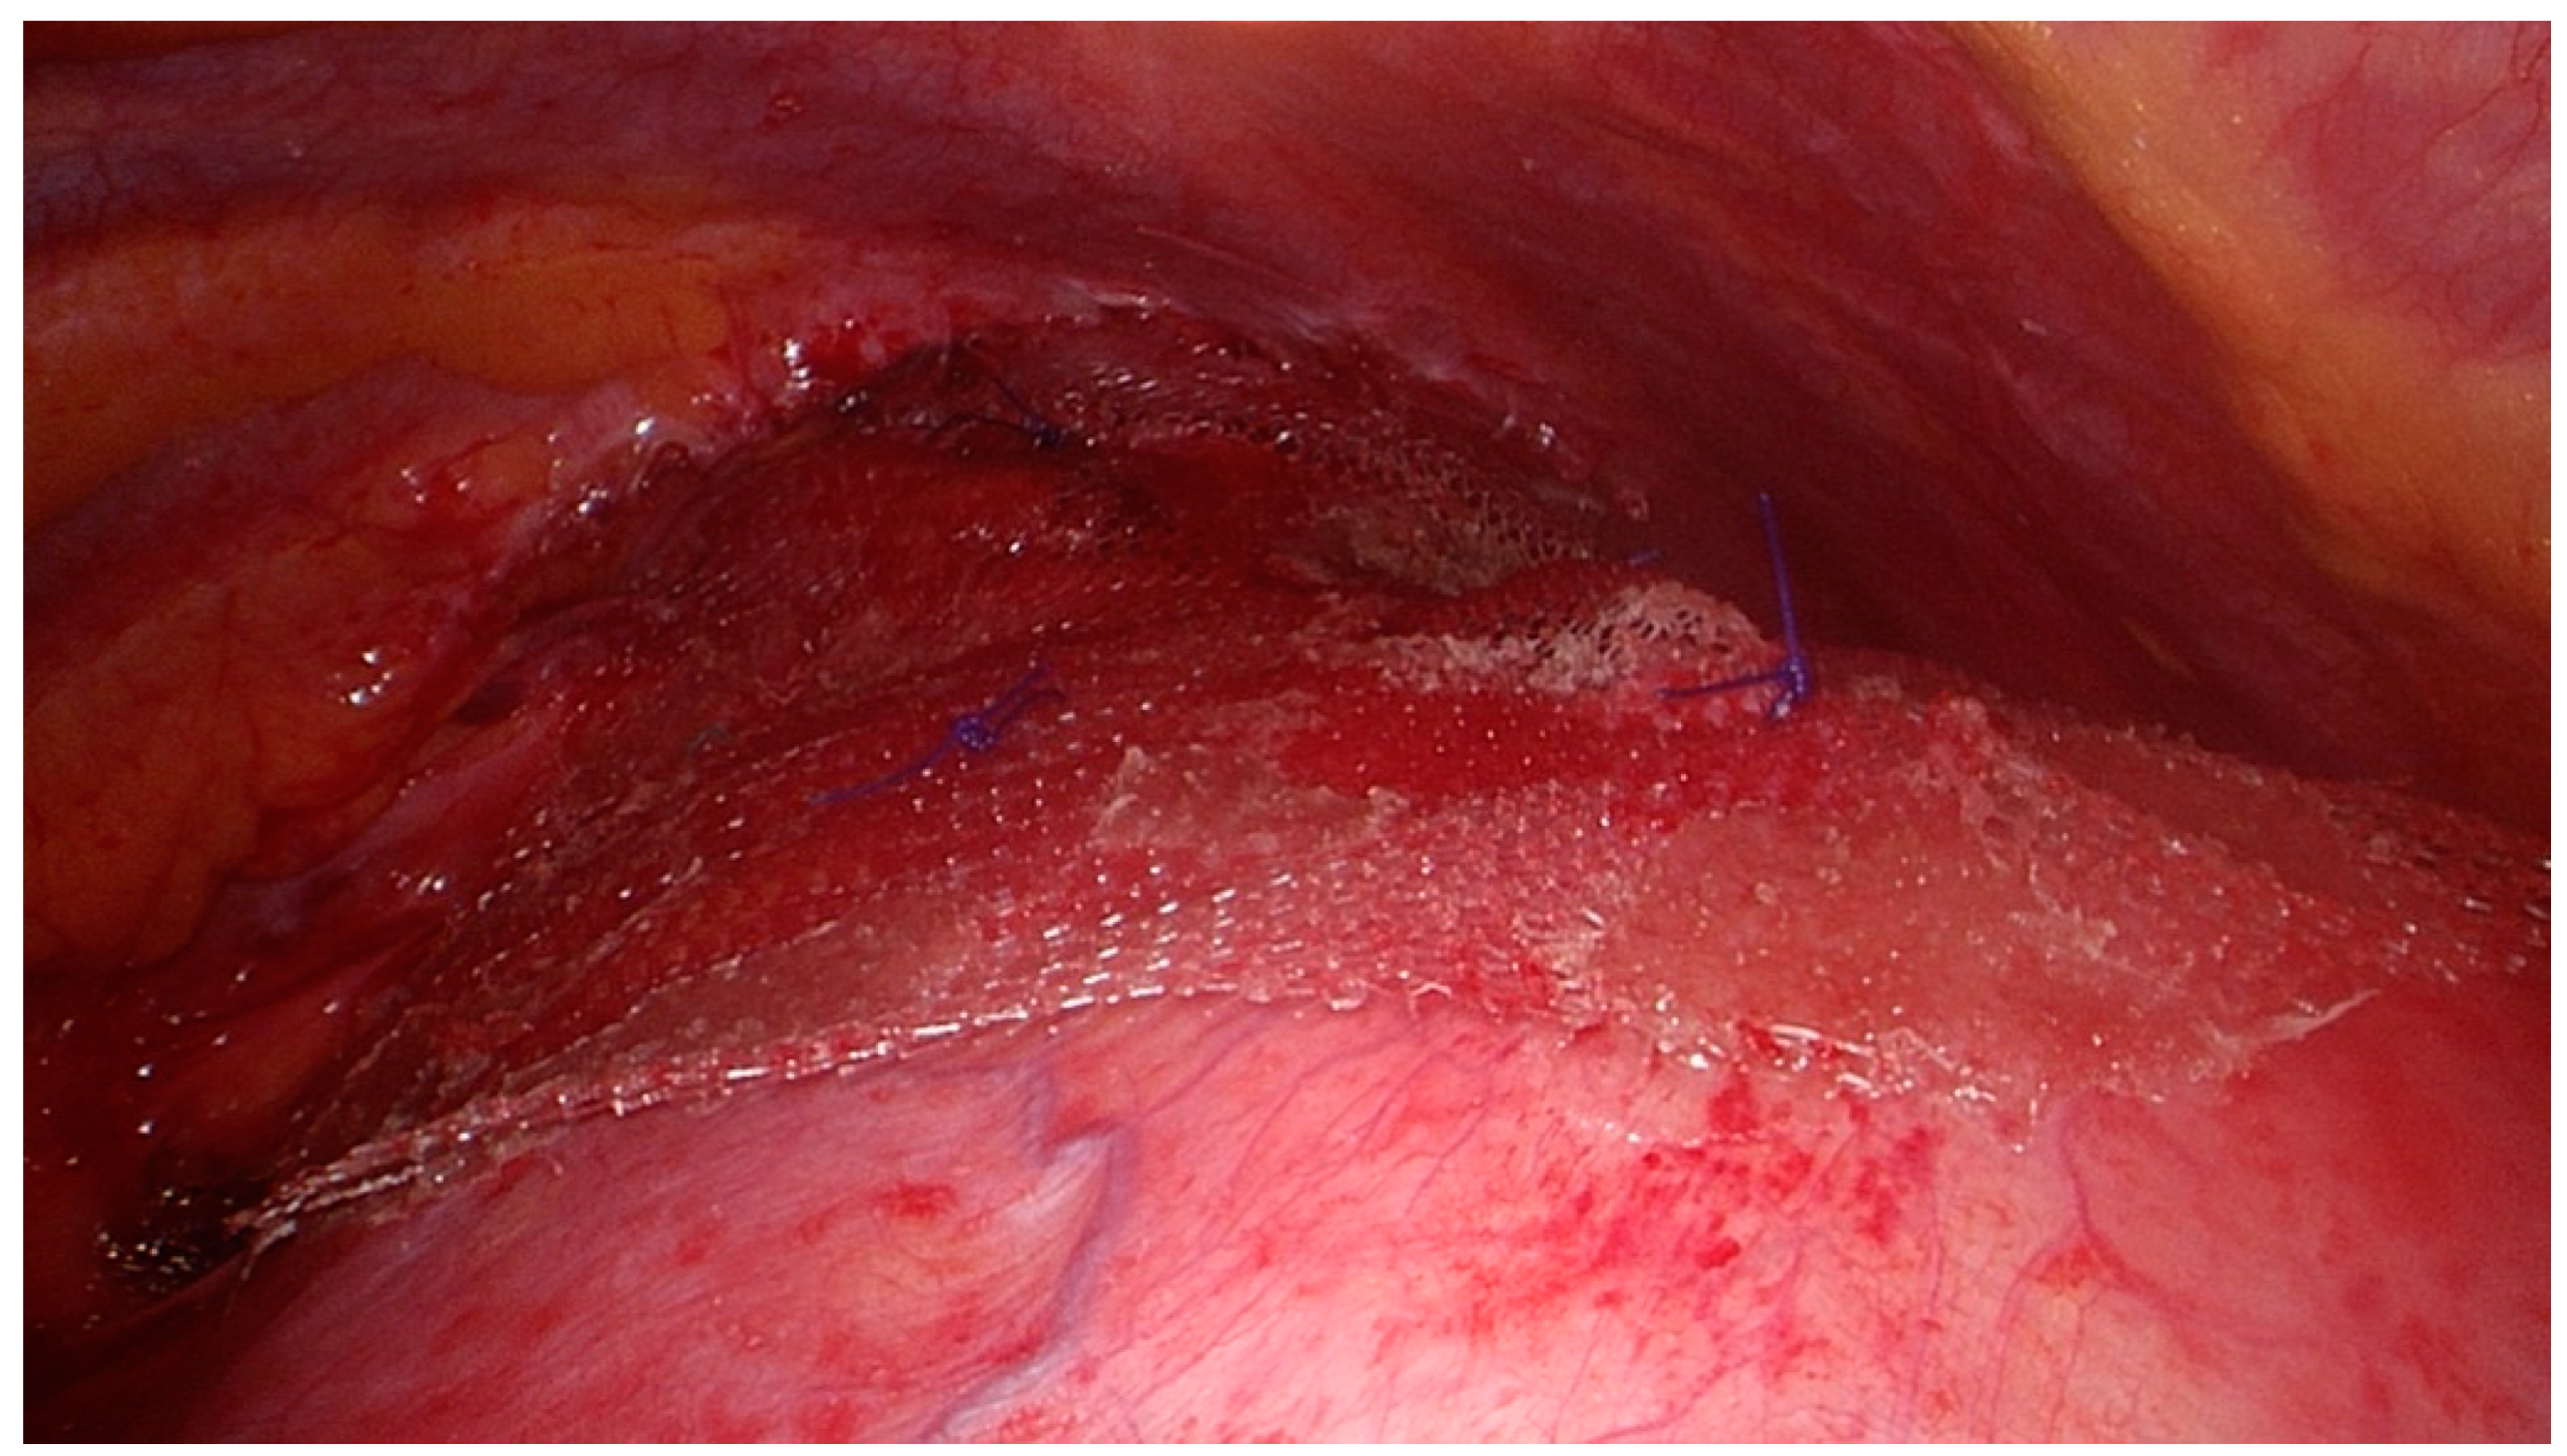

We performed a VATS procedure. The patient was placed in the right lateral decubitus position. A 5 mm 30-degree thoracoscope was introduced through a 5 mm trocar placed in the 4th intercostal space on the anterior axillary line. After exploration of the pleural cavity and identification of the hernia, two 10 mm trocars were placed in the 7th intercostal space on the mid- and posterior axillary line, respectively. Two additional 5 mm pleurotomies were performed in the 9th intercostal space on the posterior axillary line, and in the 6th intercostal space on the anterior axillary line. After reduction of the hernia, the defect was measured as 3.5 cm in diameter (Figure 3). The hernia consisted of left transverse colon that was contained in a hernial sac. It was dissected and reintegrated in the abdominal cavity. Next, the defect was closed with simple interrupted stitches of a nonabsorbable, braided suture (Ethibond 0) (Figure 4). The suture line was reinforced with a 12 cm diameter polyvinylidene fluoride (PVDF) mesh (DynaMesh®-IPOM) that was anchored with four stitches of nonabsorbable polypropylene sutures (Prolene 2-0) and surgical glue (IFABOND®) (Figure 5). We placed one chest tube (28 Fr.) with suction (−20 cmH20) at the end of the procedure. There were no intraoperative complications. Operative time was 170 min.

Figure 4.

Herniorrhaphy of the diaphragm before the application of the mesh.